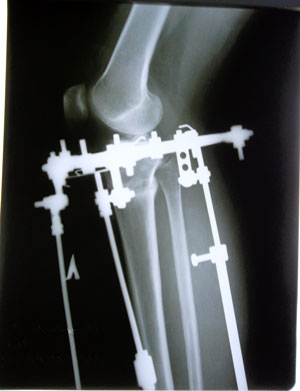

Рентген в 2 месяца с момента операции.

Вложения

SAM_8976.JPG

SAM_8977.JPG